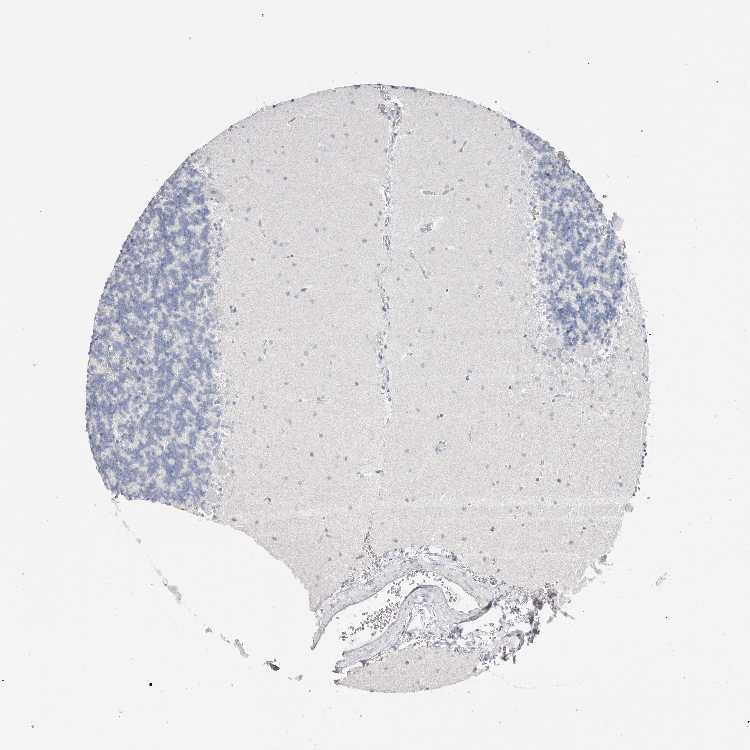

BRAIN CEREBELLUM Show tissue menu

CEREBELLUM - Expression summary

CEREBELLUM - Antibody stainingi

Antibody staining in the annotated cell types in the current human tissue is reported as not detected, low, medium, or high, based on conventional immunohistochemistry profiling in selected tissues. This score is based on the combination of the staining intensity and fraction of stained cells.

Each image is clickable and will lead to virtual microscopy that enables deeper exploration of all samples and also displays staining intensity scores, fraction scores and subcellular localization as well as patient and tissue information for each sample.

Antibody HPA038069Antibody HPA046340Antibody CAB026158

Purkinje cells Not detectedNot detectedNot detected

Cells in granular layer Not detectedNot detectedNot detected

Cells in molecular layer Not detectedNot detectedNot detected